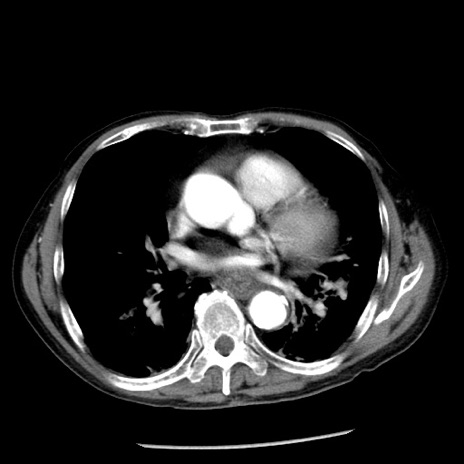

症例26(横断像)

【症例】80歳代男性

【主訴】嘔吐

【現病歴】昨晩2回嘔吐あり、今朝になっても嘔吐あり。来院。

【既往歴】胃潰瘍

【身体所見】意識清明、BT 37.6℃、BP 166/95mmHg、HR 100bpm、SpO2 97%、腹部:平坦・軟、腸蠕動音聴取良好、圧痛なし。

【データ】WBC 21900、CRP 1.46